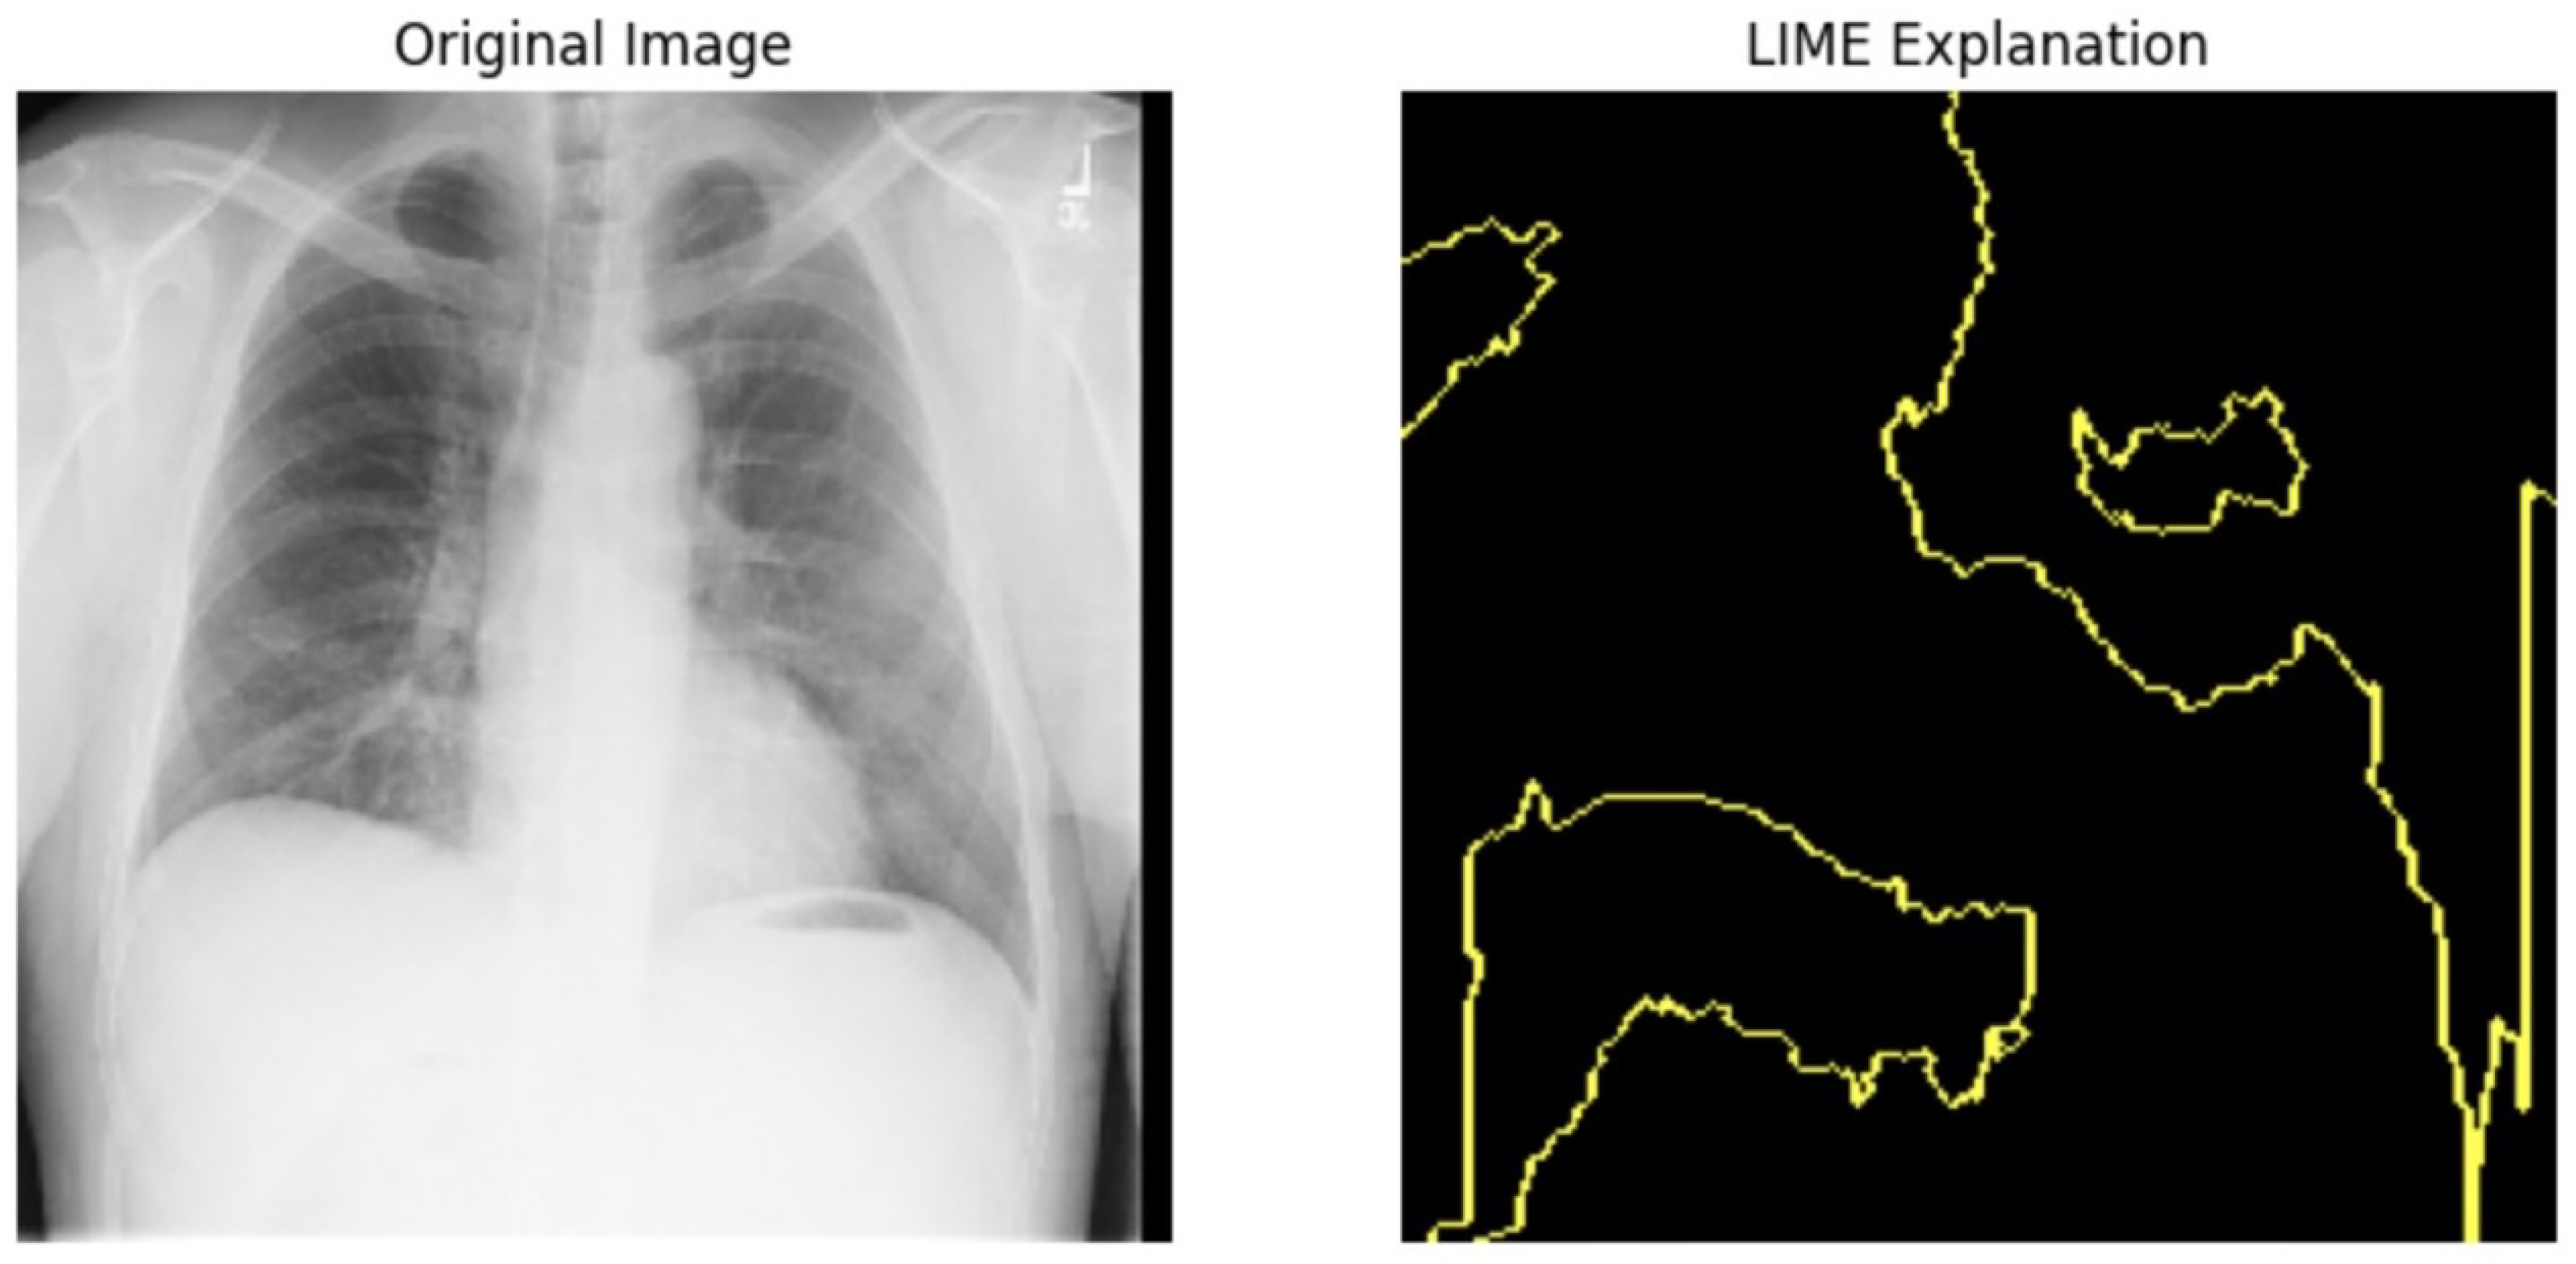

5.4.1. Local Interpretable Model-Agnostic Explanations for Clinical Validation

We applied scientific analysis on a random 7 sample, which was provided by the clinical specialist. The LIME Analysis for Image Data (a), (b), (c), (d), (e), and (f) is in Figure 22, Figure 23, Figure 24, Figure 25, Figure 26 and Figure 27. There are two parts of LIME analysis from the provided chest X-ray images to detect the disease area. Original Image and LIME explanation;

• Original Image: The patient’s thoracic cavity. It displays the typical anatomical structures of the chest, including the lungs, ribs, and heart.

• LIME Explanation: The result of applying LIME to the chest X-ray image. The yellow boundaries indicate the regions of the image that were most influential in the model’s decision-making process when determining whether the image indicated a particular condition. In this context, these regions are the parts of the X-ray that the AI model considered most important for making its diagnostic prediction.

The analysis very useful for clinicians to understand the model’s behavior and ensure that it aligns with medical expertise. The use of LIME helps in making the AI model’s interpretability decisions more transparent and interpretable. It allows medical professionals to verify whether the AI’s focus areas correspond to clinically significant regions. It also enhanced diagnostic capability of understanding which parts of the images in the AI model in refining the model further and ensures that it makes accurate and reliable predictions. This is particularly crucial in medical diagnostics where interpretability and accuracy are paramount.

Figure 22. LIME Analysis for Image Data (a) on original image to LIME explanation.

Jpm 14 00856 g022